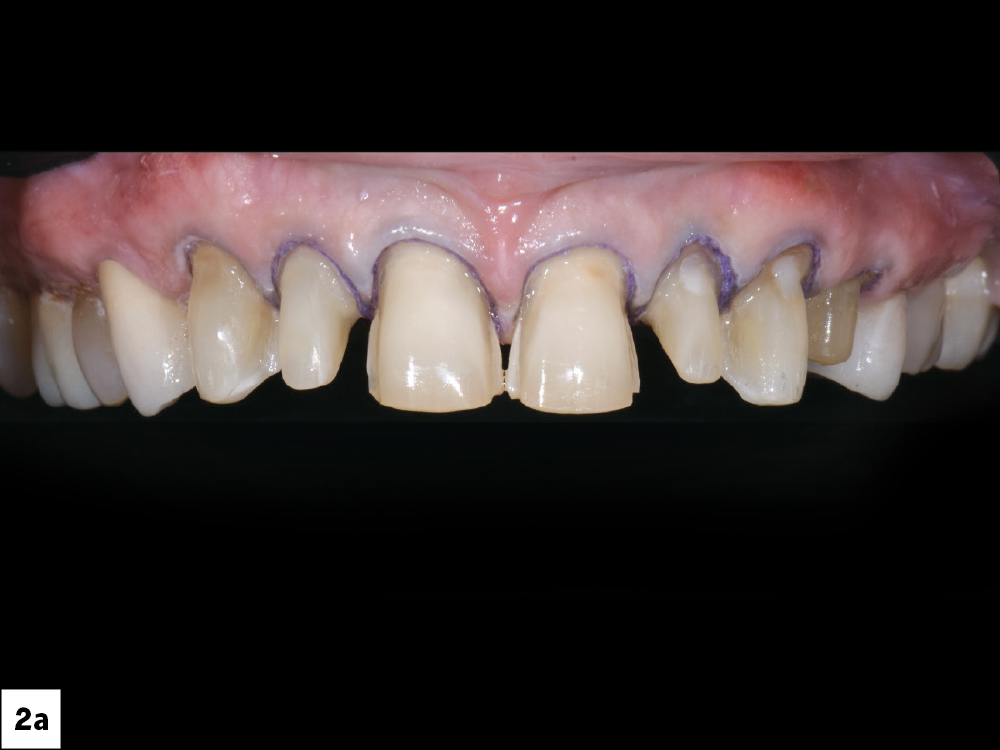

Preparations were completed for teeth #6–12

A gingivectomy was performed on teeth #8 & #9

Figures 2a, 2b: A gingivectomy was performed on teeth #8 & #9 to create longer central incisors, as the gingival levels of the laterals were initially slightly higher than the centrals. Preparations were completed for teeth #6–12, and double retraction cords (00 and 0) were placed into the sulcus for optimal margin capture. The digital impression was taken with the iTero Element® 5D Plus intraoral scanner. I determined that a combination of crowns, veneers and an onlay would serve as the definitive treatment plan.